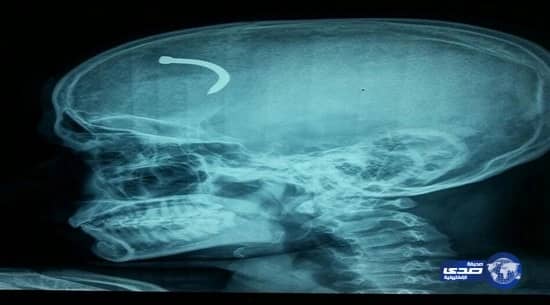

أجريت جراحة ناجحة لمقيم هندي بمستشفى الأمير عبدالعزيز بن مساعد بمدينة عرعر في أعقاب اختراق مسمار جداري عظام الجمجمة ليستقر بعدها في أنشطة الدماغ.

اتضح أن المريض يعمل بالخازق الكهربائي ووضع مسمارًا في الجدار فاختل توازنه وحدث ارتداد قوي للجهاز أدى إلى انعكاس المسمار الجداري واخترق عظام الجمجمة من الجبهة ناحية الجهة اليمنى فوق حجاب العين واستقر في أنشطة الدماغ.

يذكر أن الطبيب الذي باشر الجراحة هو الدكتور محمد جهانقير استشاري جراحة المخ والأعصاب والذي قام بفتح عظام الجمجمة وأزال المسمار من أغشية الدماغ الداخلية.